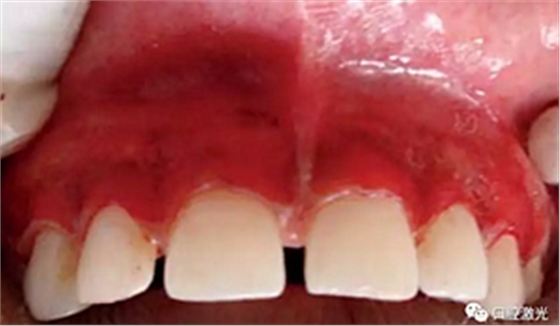

术后一周

术后三月